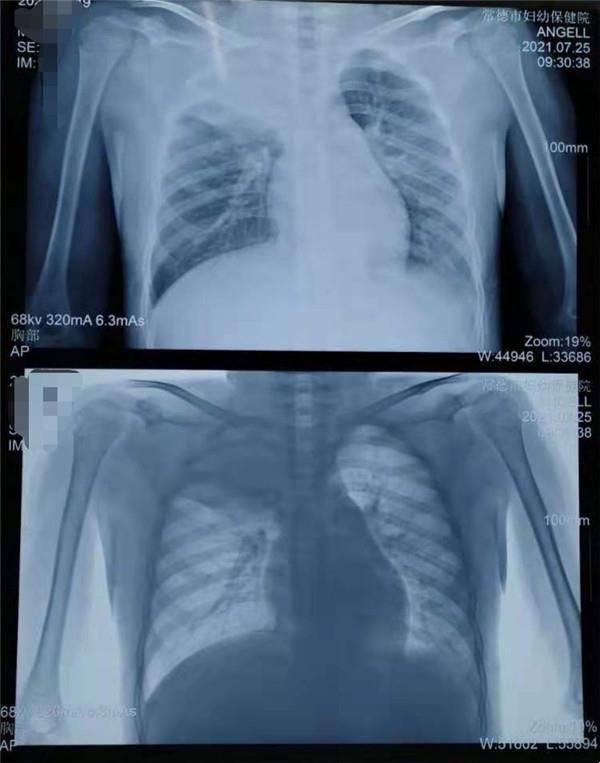

8歲的男孩浩浩(化名),因持續(xù)發(fā)熱、咳嗽,近一個(gè)星期也不見(jiàn)好轉(zhuǎn),在家長(zhǎng)的帶領(lǐng)下到常德市婦幼保健院兒科就診,擬“社區(qū)獲得性肺炎(重度)”收住院治療,兒科醫(yī)療團(tuán)隊(duì)制定了周密的診療計(jì)劃,經(jīng)積極抗感染、化痰止咳、退熱、霧化等處理,浩浩發(fā)燒的癥狀雖有所好轉(zhuǎn),但咳嗽加重,呼吸困難明顯,肺實(shí)變加重。

胸部X片:右上肺及左下肺大片高密度影